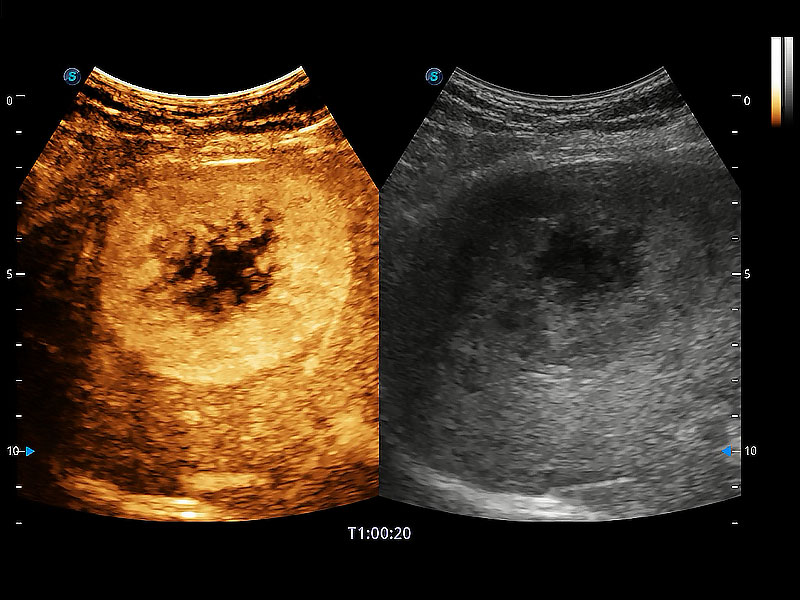

操作简便,无需高频度外力作用即可真实反映组织的形变,快速评估肿瘤良恶性。

非线性融合造影成像充分利用谐波和基波信号,为难以观察的血流进行增强显像。可用于线阵、凸阵、微凸阵、相控阵探头。